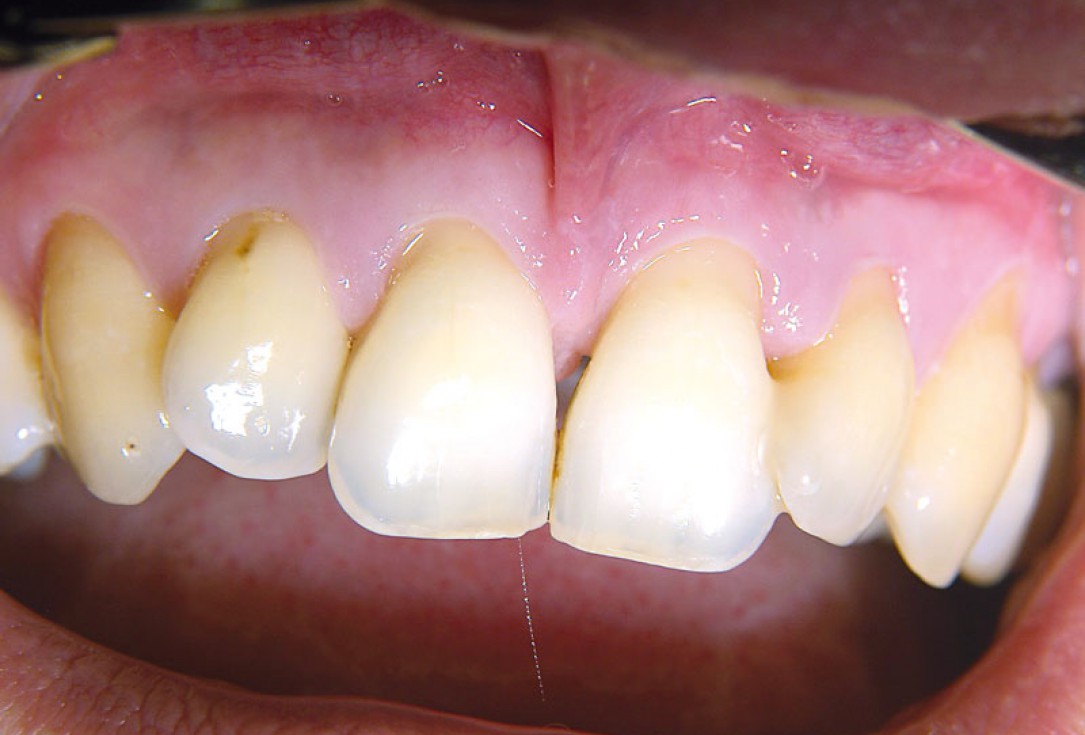

02/11 - Baseline clinical situation.Non-contained intrabony defect treated using cerabone®, collprotect® membrane and Straumann® Emdogain® - Dr. T. Schwaar (2)